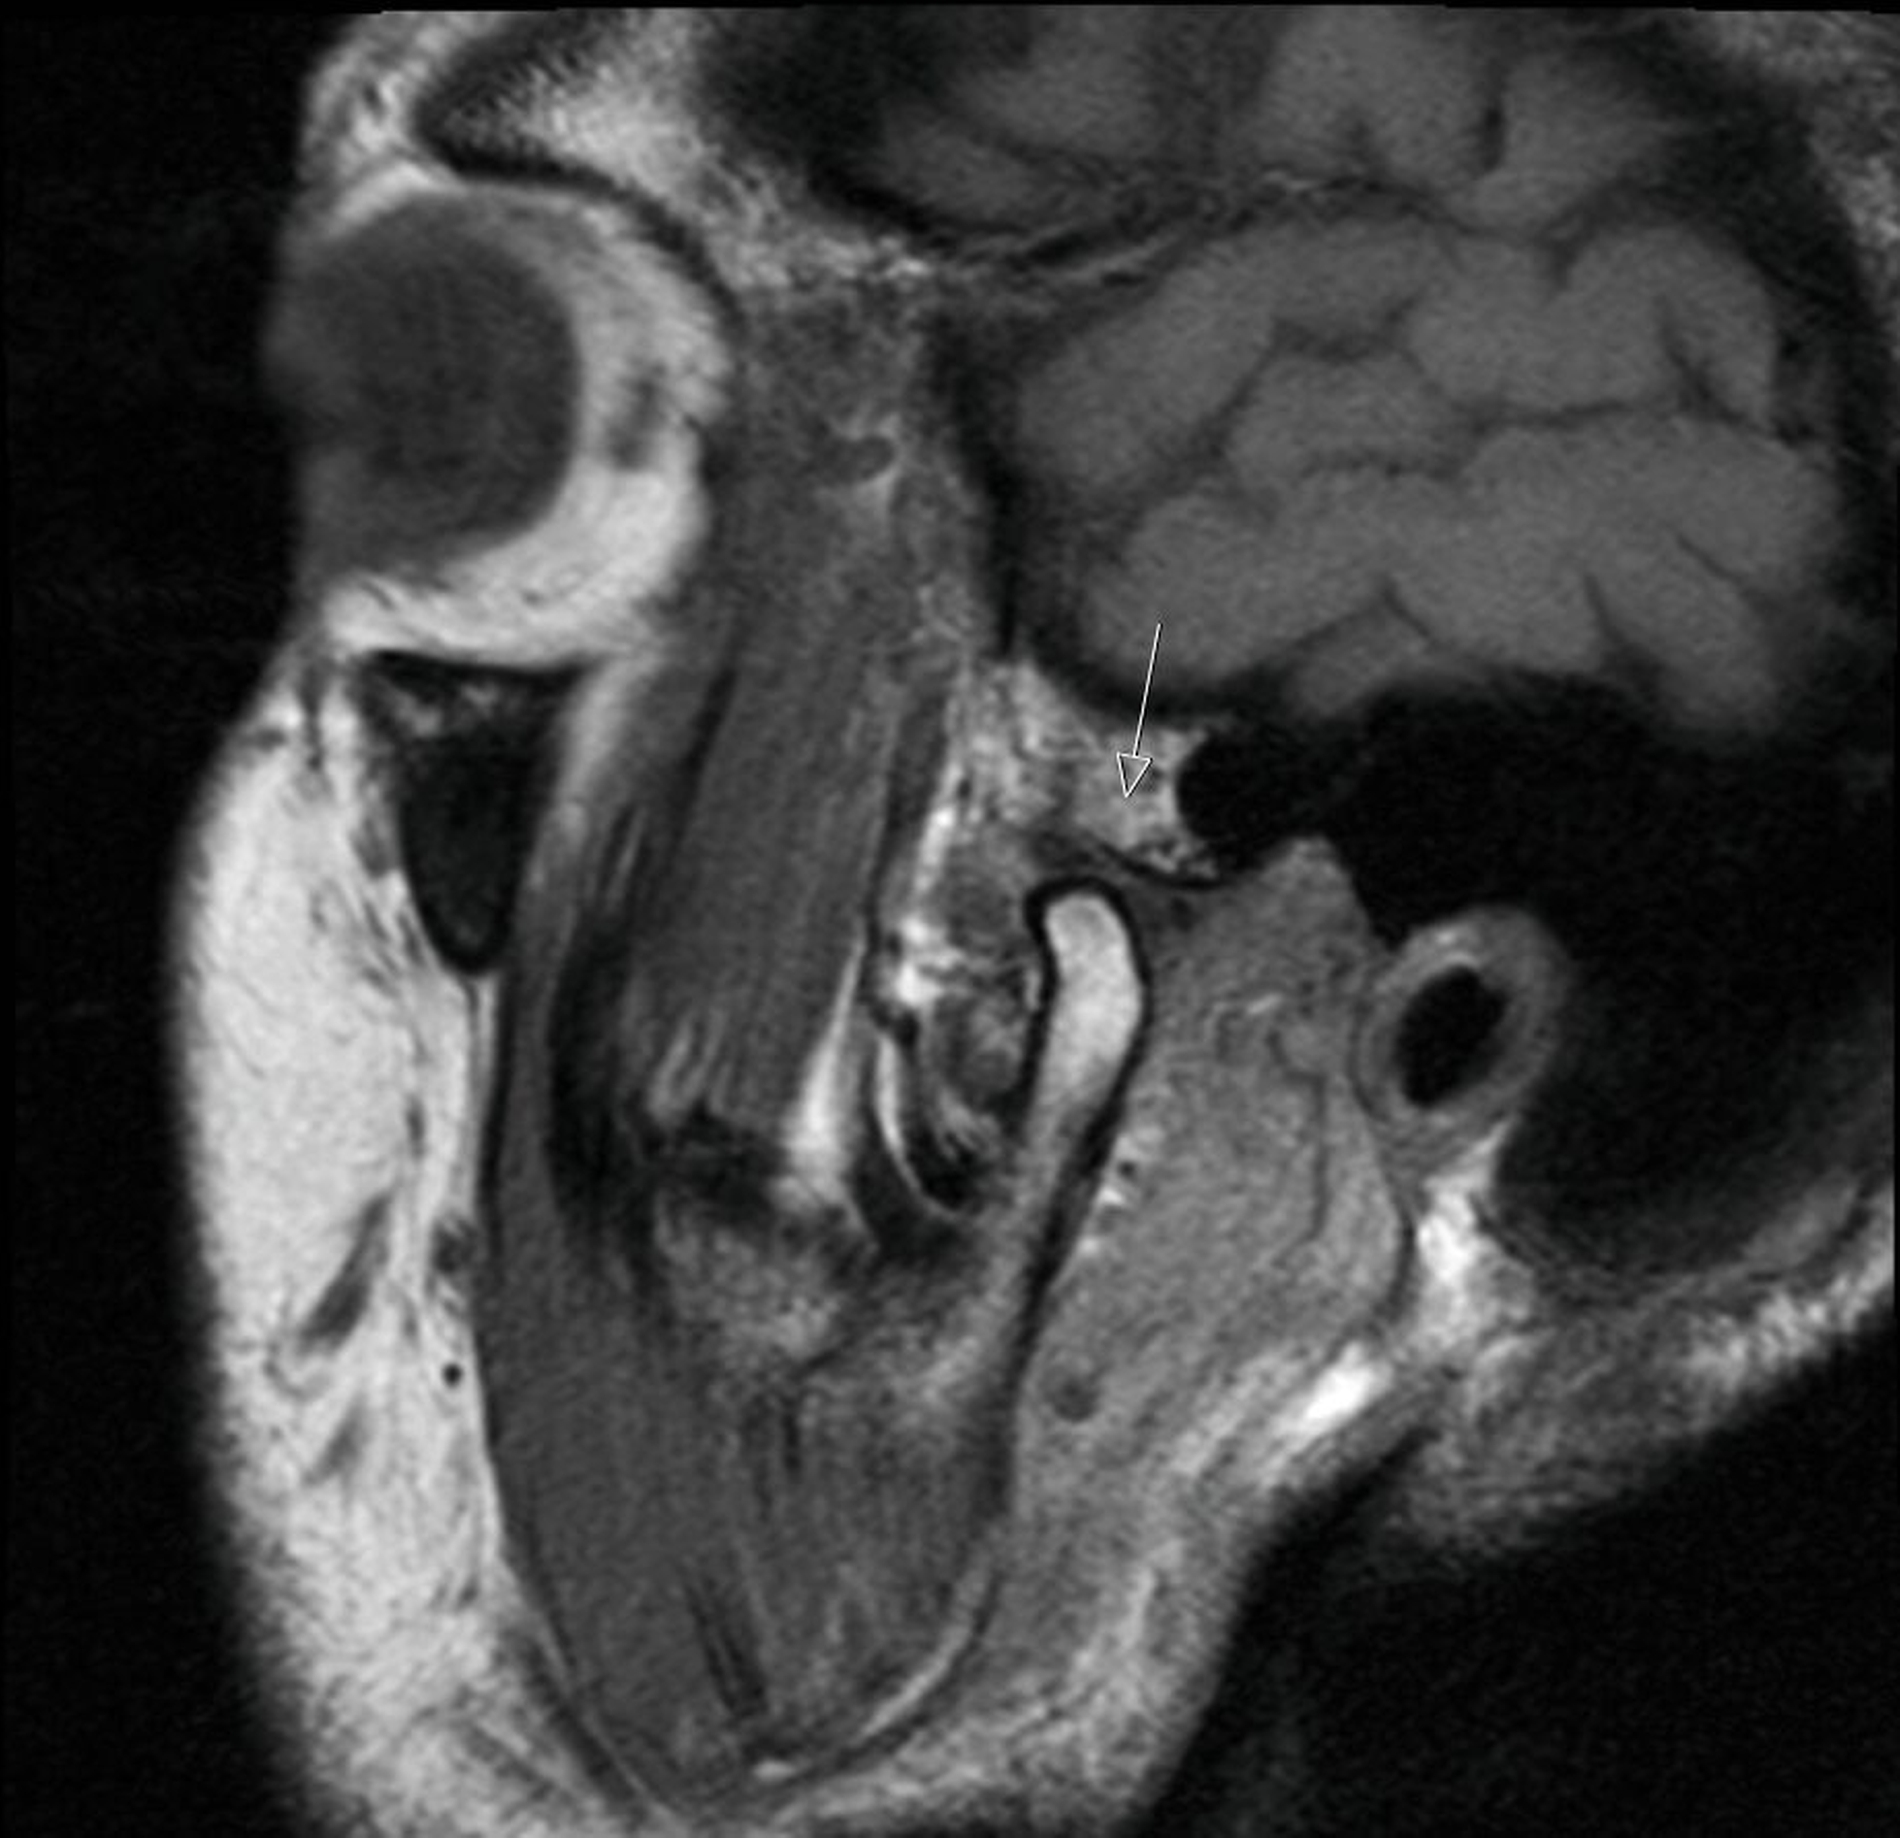

Bei der klinischen Inspektion zeigt sich eine erythematöse, narbig imponierende Hautveränderung präauriculär im Bereich der Kiefergelenke beidseits. Zusätzlich waren eine Hyperkeratose und eine schuppige Komponente zu erkennen (Abbildungen 1 und 2). Auf Palpation zeigte sich der präauriculäre Bereich auf Höhe der Kiefergelenke druckdolent. Während der Funktionsdiagnostik war der rechte Condylus mandibulae deutlich hypermobil. Knack- oder Reibegeräusche waren nicht zu hören. Gleichzeitig war eine Deviation zur linken Seite bei der Mundöffnung zu beobachten. Die orale Mundschleimhaut erschien unauffällig bei Abwesenheit von Blasen oder Erosionen. In der alio loco angefertigten MRT-Aufnahme, die durch den Hauszahnarzt entsprechend der aktuellen Literatur [Schmidt et al., 2022; Neff, 2021] angefordert und vom Patienten mitgebracht wurde, zeigte sich die Struktur des Gelenks und des Diskus regelrecht (Abbildungen 3 und 4). In den Aufnahmen während der Kieferöffnung war lediglich eine Hypermobilität des rechten Condylus mandibulae zu erkennen (Abbildung 5). In der T1-Wichtung waren keine Infiltrationen oder entzündliche Veränderungen des präauriculären Weichgewebes zu sehen.